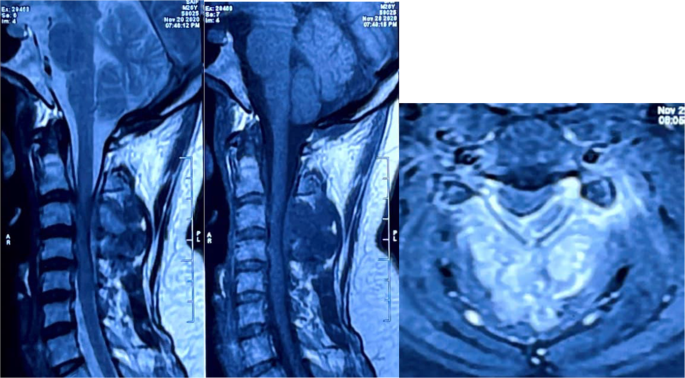

First, the shape, nature, and growth of the gills are examined in detail. For that, X-ray, video X-ray, CT scan and MRI are done.

If it looks suspicious, a biopsy should be done to check the meat.